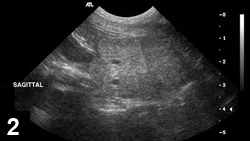

A sagittal ultrasound image displays a cross-section of an animal's abdomen, revealing various internal structures with varying echogenicity. The image includes measurement markers on the right side, indicating depth and scale for clinical assessment.

FIGURE 2

CBPH sagittal view (ventral is top of image, cranial is left) of a canine prostate with small anechoic parenchymal cysts.

• Characteristic appearance of BPH and CBPH on ultrasonography includes symmetric parenchymal striation with increased echogenicity and variable hypoechoic-to-anechoic intraparenchymal cystic structures (Figures 1 and 2).